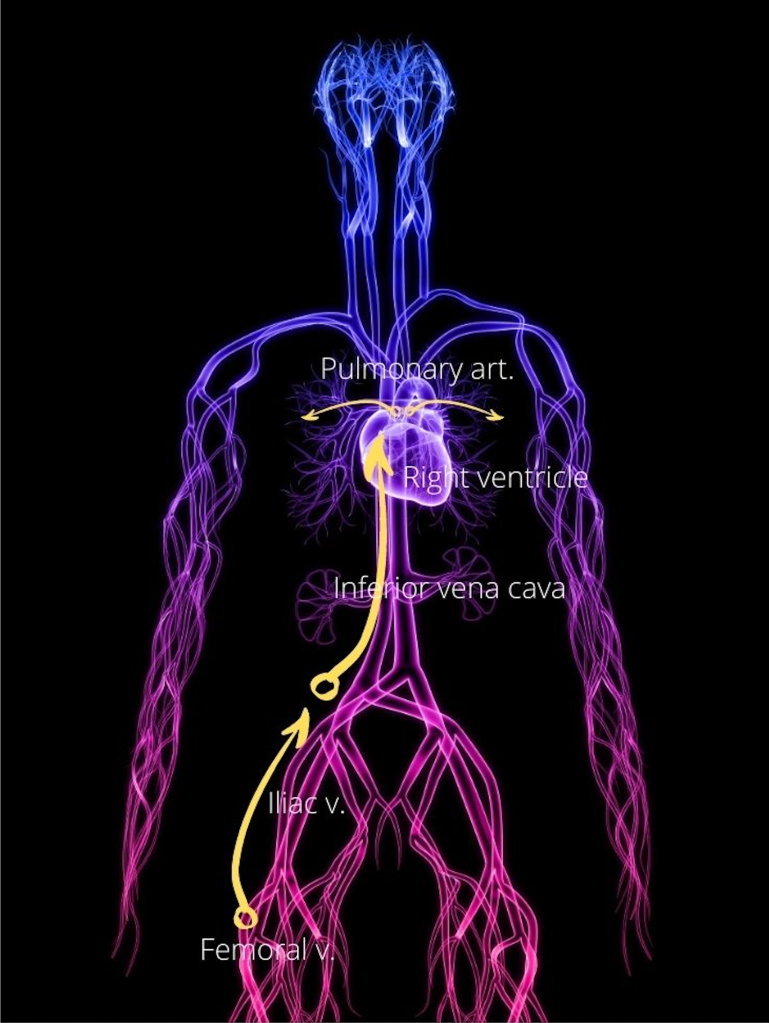

The movement follows the blood stream and the thromboembolus impacts at the narrowest point relative to the size of the embolus. Therefore, it follows that venous thromboemboli impact in the pulmonary vasculature after it has moved through the large veins and right cardiac chambers. Arterial thromboemboli though will impact in the smaller branches of the arteries.

The most common source for VTE is from the deep veins of the leg. As explained in the earlier blog, thrombosis involving the leg veins is known as deep vein thrombosis (DVT).

Whatever the source, the dislodged venous thrombi will move through the large bore inferior or superior vena cava, and then pass through the capacious right atrium and ventricle into the pulmonary artery. Here the calibre of the arteries begin narrowing. Depending on the size of the emboli, it may therefore become impacted in the pulmonary trunk if large, or move distally to impact in the smaller branches of the pulmonary artery. Venous emboli that becomes trapped in the pulmonary artery and its branches is called pulmonary thromboembolism (PE).